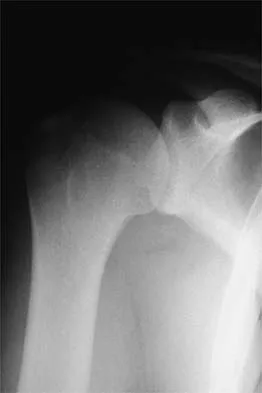

Figure 37 shows the radiograph of a 23-year-old football player who sustained a blow to the anterior aspect of his shoulder. Examination reveals pain and limited rotation. He is unable to flex the arm above the shoulder. Management should include which of the following studies?